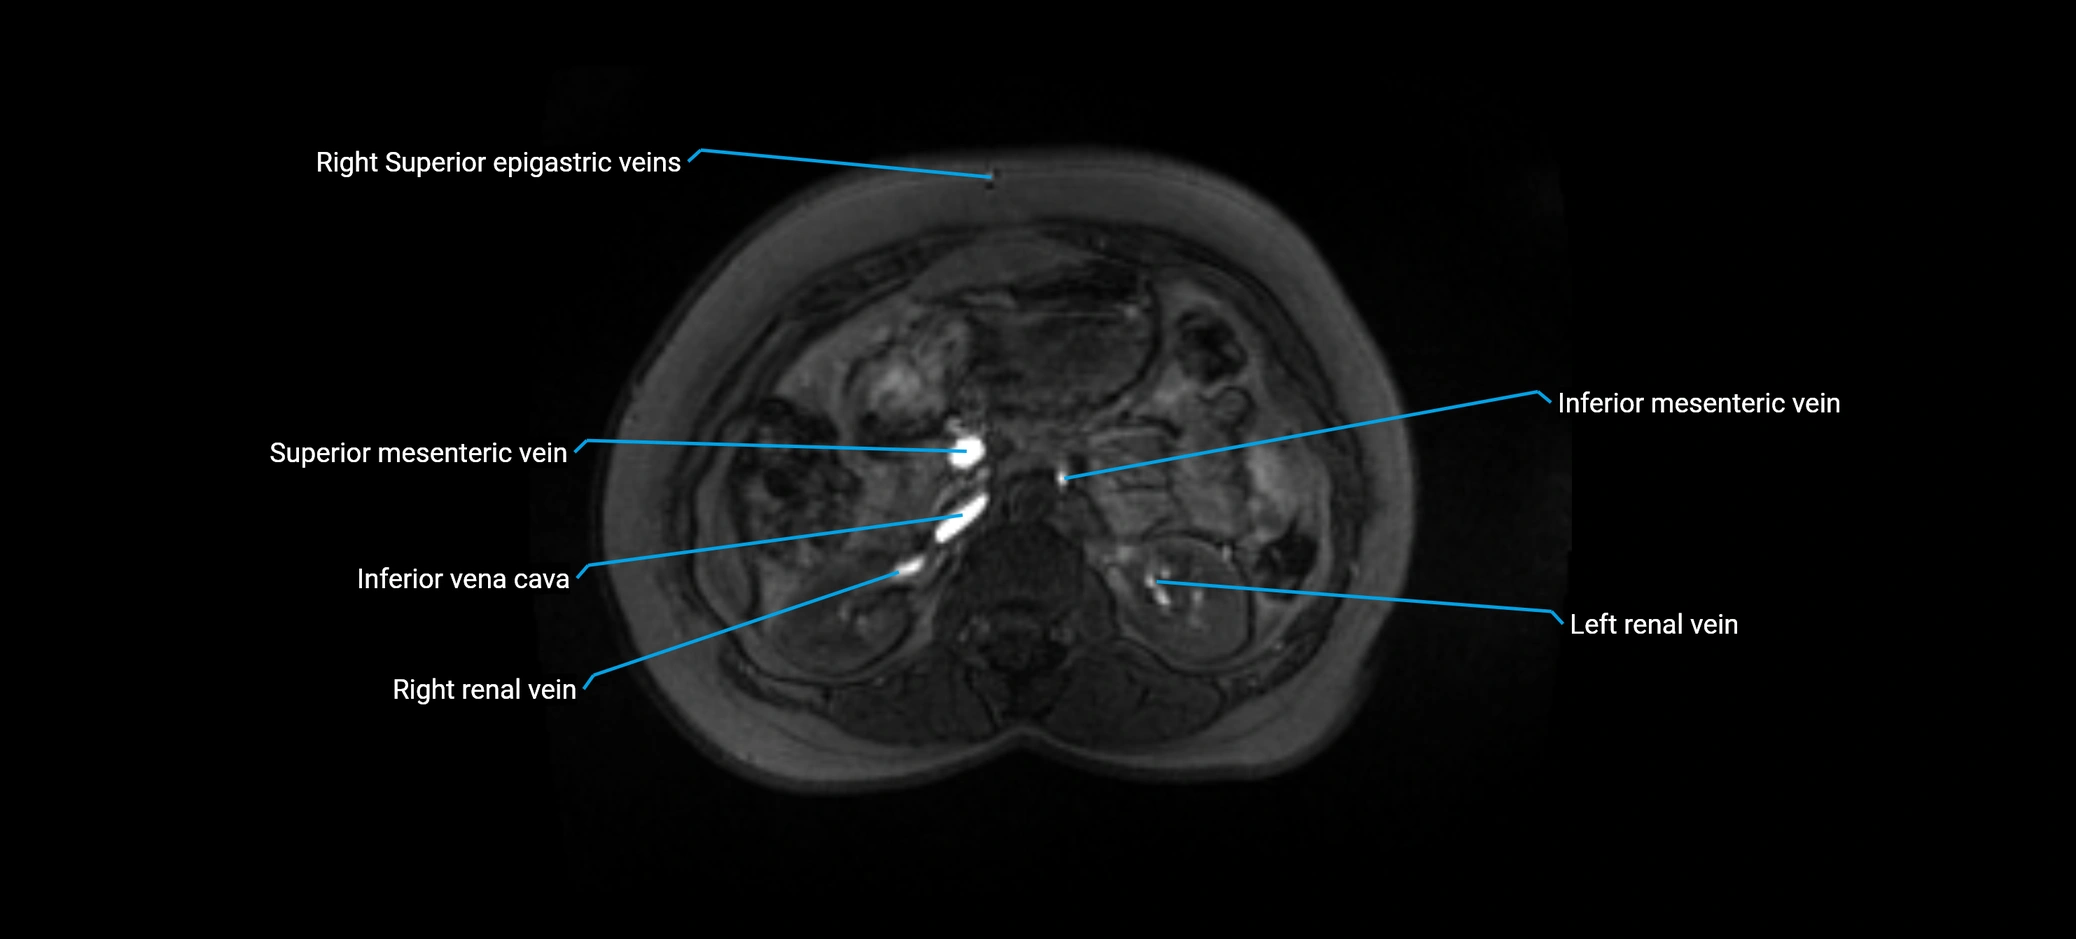

MRI image

image